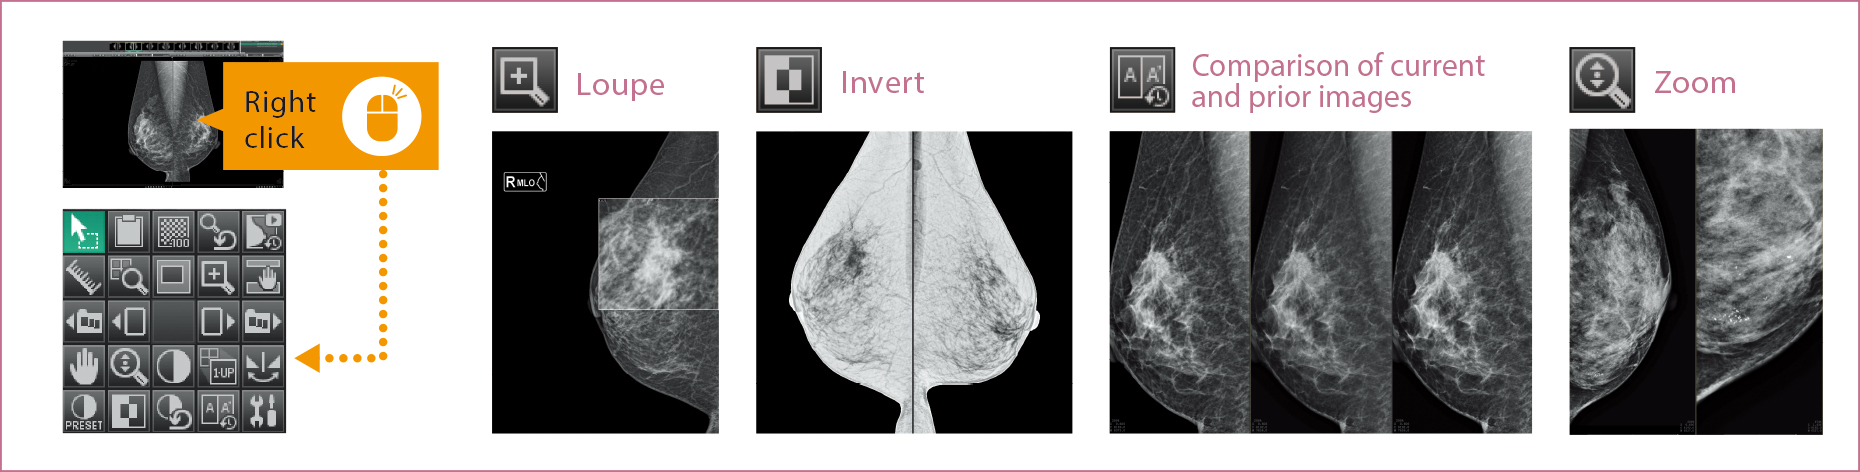

Support for users in conducting diagnosis with reading protocols tailored to mammographic diagnosis and smooth image displays. Customization for reading protocols includes configuration for making comparisons of current and prior images and for S-views synthesized from tomosynthesized images of AMULET Innovality and AMULET SOPHINITY.

The results from multiple exams for a patient are displayed in a list. Users can switch the displayed image with one of the selected images.

The thumbnail window allows users to instantly see all the images taken for each individual exam in a single one view. Each image can be easily selected and displayed by dragging and dropping.